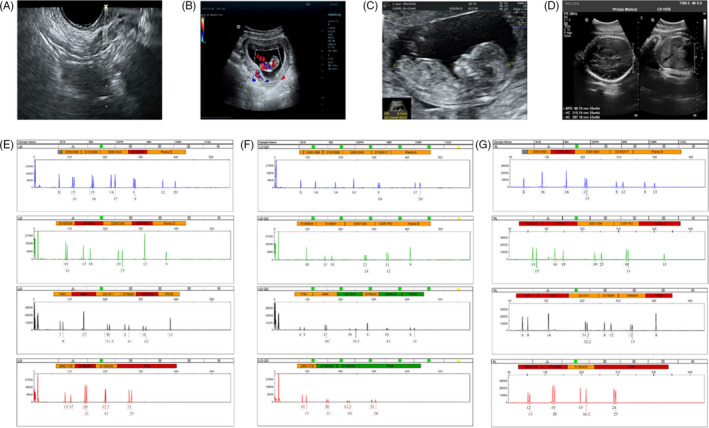

收集了15名接受取卵的患者的基本特征,包括取卵周期、胚胎移植和妊娠次数。一般来说,四个胎儿没有出生缺陷,三个胚胎来自ICSI的受精类型,而最后一个是自然受孕的。1例术中超声扫描显示,在经阴道超声(TVUS)引导下,卵巢未见间质增生或其他异常卵巢结构(图2A)。这名妇女在体外受精后成功怀孕,并在第8周进行了基本产前程序的超声扫描(图2B),第13周(图2C) 和第32周 (图二维) 显示正常的胎儿发育。微卫星位点分析显示,胎儿(图2F)与母亲有遗传关系(图2E) 供体UCMSC以外的其他人(图2G)。